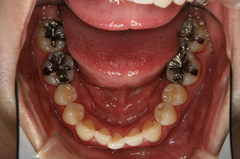

写真は初診時ですが、プラークコントロールがあまりよくなく、虫歯や歯肉の炎症が全顎的に認められました。

歯肉の炎症がこれだけ強いとすぐに出血してしまうため、確実な虫歯の治療ができないことをお伝えし、まず患者さんにはブラッシングを徹底してもらいました。